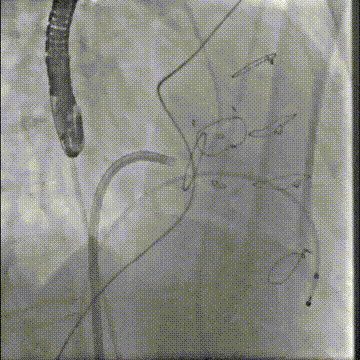

切割前:左室压 110 左房压 58,切割时需要时刻监测左室压,以保证guiding头端在左室内,防止电流接触主瓣

40w的电凝进行切割,2-3次,每次不超过10秒。

切割时拉紧导丝两端,不切割时,放松导丝,解除对瓣叶的压力后,用彩超观察血流方向,切割成功后,可以观察到彩超血流的改变。

确认Lampoon技术成功后,保留全轨情况下二尖瓣环内放入超硬导丝至左心室